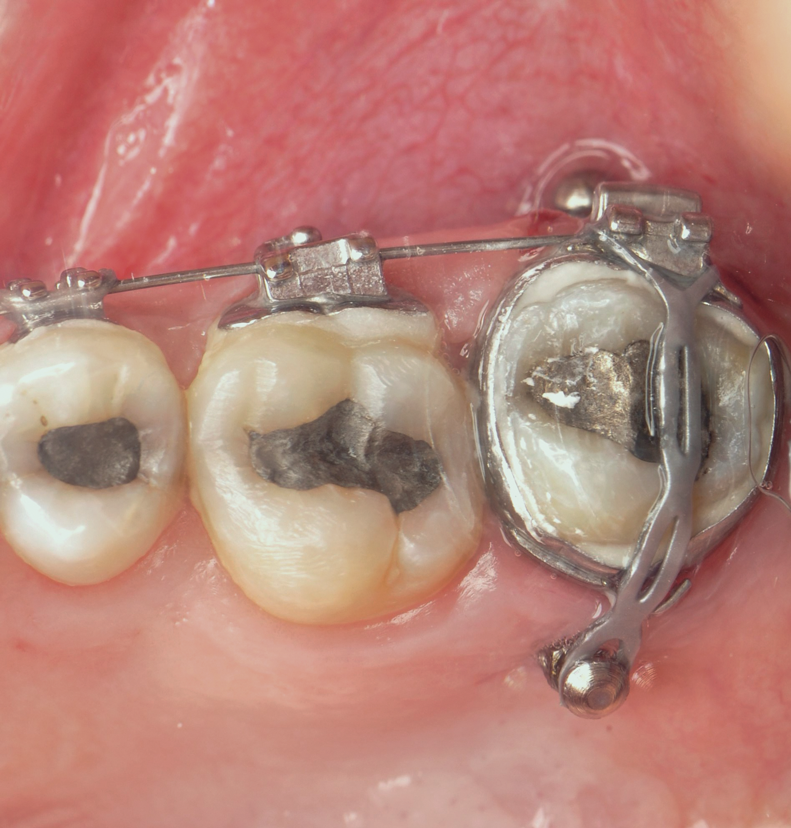

Fig 3. TAD-assisted intrusion. Buccal and palatal TADs were used to intrude an overextruded molar in a class II surgical patient.

Figure 3